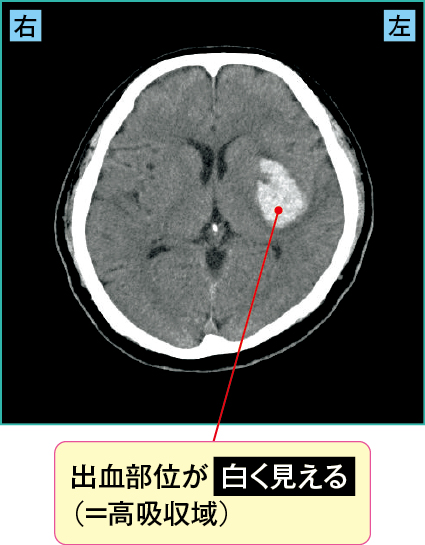

1)被殻出血の画像の見方

図2は被殻出血の画像です。出血部位が白く見える“高吸収域”が確認できます。

図2 被殻出血(CT)

責任血管は中大脳動脈(MCA)から分岐するレンズ核線条体動脈です。

被殻は運動神経の通り道である内包が近いため(図2)、反対側の運動麻痺が現れます(機能局在は脳画像の読み方入門:図で学ぶ脳の構造を参照)。図2の症例では、左の内包が障害され、右半身の運動麻痺が出現していました。

また視床まで出血が及ぶと感覚障害が出現することがあります。